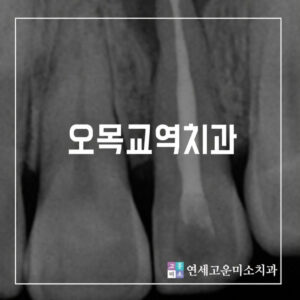

특히 교정 초기에 치아 상태를 정밀하게 진단하고,

치료 계획을 잘 세우는 것이

후속 치료 기간에 큰 영향을 미칩니다.

방학 중 교정치료를 시작하면 초기 정밀검사와 장치 부착,

잇몸 상태 확인 등 중요한 첫 단계를

충분한 시간 여유를 두고 마무리할 수 있습니다.